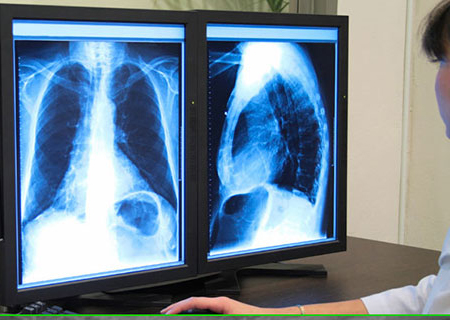

Los rayos X que atraviesan los tejidos quedan registrados en una película o una placa detectora de radiación, produciendo una imagen que muestra los distintos grados de densidad de los tejidos. Cuanto más denso es el tejido, más rayos X bloquea y más blanca será la imagen:

- El hueso aparece casi blanco.

- La grasa, el músculo y los líquidos aparecen como sombras en diferentes tonos de gris.

- El aire y el gas aparecen en color negro.

- Neumonía: el aire del interior de los pulmones (de color negro), contrasta claramente con los tejidos infectados (de color blanco), que bloquean los rayos X.